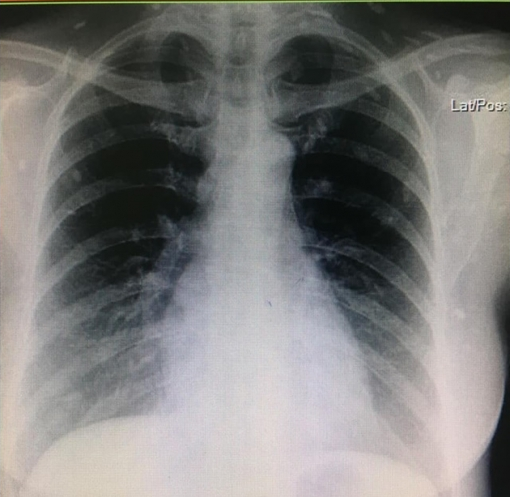

Bác sĩ đã thực hiện một số xét nghiệm và chụp X-quang cho anh Lim. Kết quả thực sự khiến bác sĩ cũng phải sốc. Hình ảnh chụp X-quang cho thấy gan của ông Lim có rất nhiều kí sinh trùng sinh sống và đang bò lổm ngổm. Anh được chẩn đoán mắc bệnh sán lá gan, còn được gọi là Clonorchis sinensis, một loại giun ký sinh. Tình trạng nhiễm trùng giun kí sinh ở người thường xảy ra sau khi ăn cá hoặc cải xoong nước ngọt bị ô nhiễm hoặc nấu chưa chín. Những ký sinh trùng này có vòng đời rất dài, một khi chúng đến tuổi trưởng thành và thường sống 20-30 năm bên trong vật chủ (cả cơ thể con người).

Hình ảnh chụp X-quang của bệnh nhân này đã khiến người khác rất số. Nó cho thấy 2 chân của cô phủ đầy những đốm trắng và người ta tin rằng những đốm này là ấu trùng của ký sinh trùng mà người phụ nữ đã ăn.

Rõ ràng, người phụ nữ rất thích ăn thịt lợn sống và đã ăn nó khá lâu. Tuy nhiên, một ngày nọ, cô cảm thấy không khỏe và đã đến bác sĩ để kiểm tra. Bác sĩ đã tiến hành chụp một số hình ảnh X-quang cho cô và bị sốc khi nhìn thấy những hình ảnh của chân cô, đầy những đốm trắng. Khi kiểm tra kĩ hơn, bác sĩ kết luận rằng cô bị nhiễm giun ký sinh do thói quen ăn thịt lợn sống có thể bị nhiễm ký sinh trùng. Có vẻ như ấu trùng từ giun đã có thể đi qua đường ruột và tiến hành lây nhiễm các bộ phận khác của cơ thể bao gồm cả cơ bắp, nơi chúng sẽ ở lại.